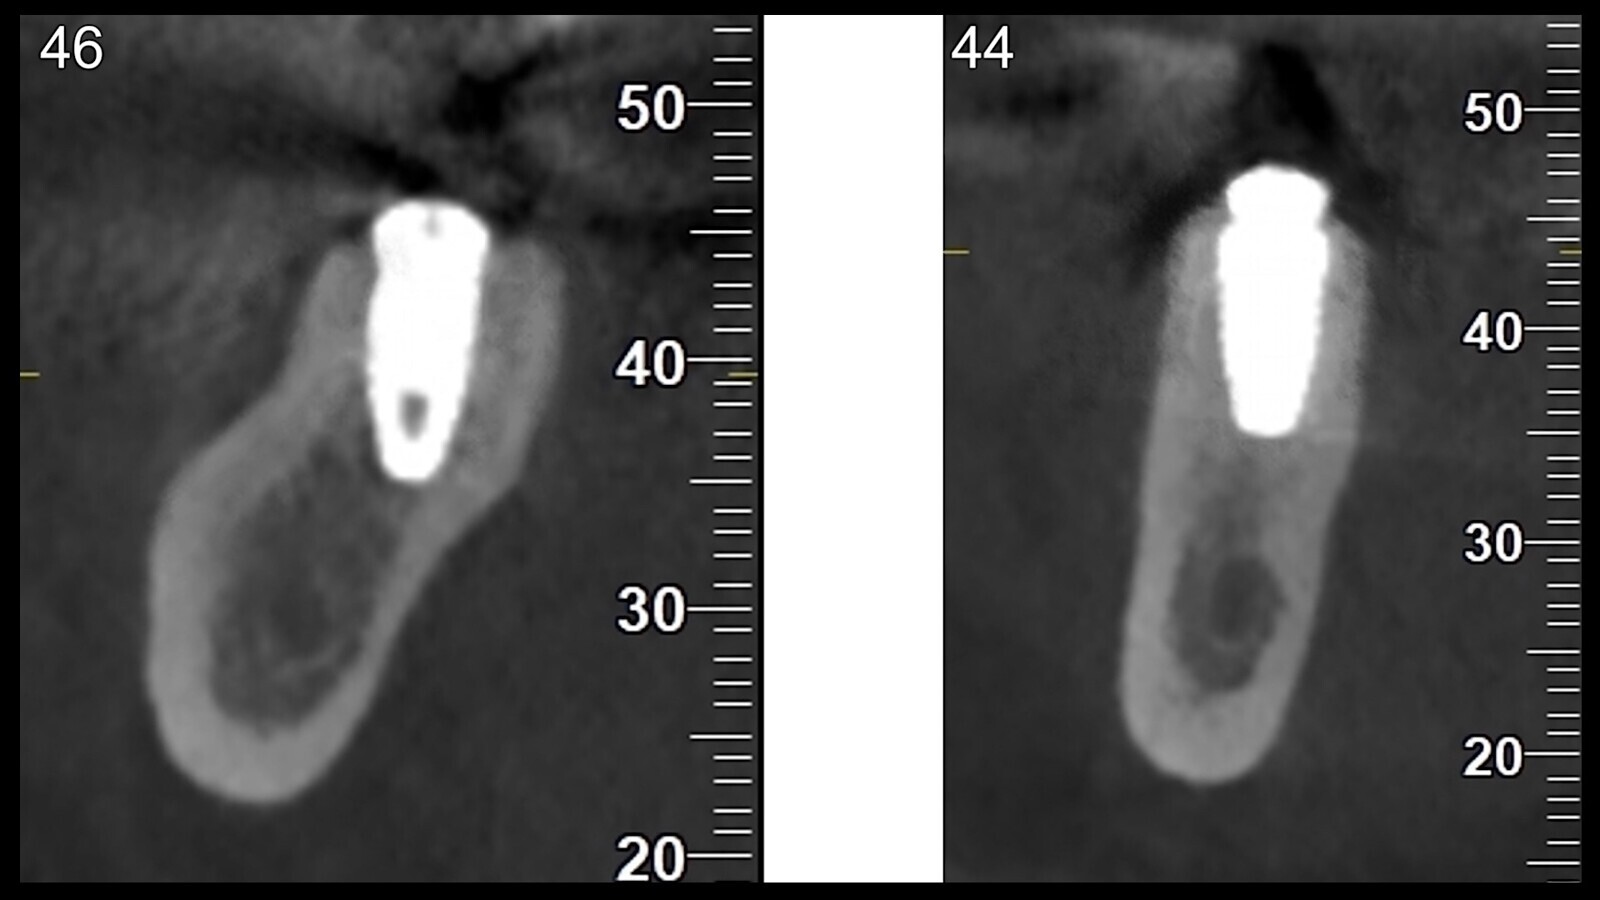

La radiografía postoperatoria confirmó la correcta colocación del implante (Fig. 9).

Fig. 9. CBCT que muestra la colocación correcta del implante en las posiciones 46 (izquierda) y 44 (derecha).